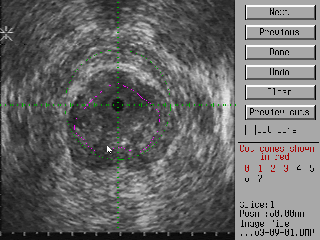

Having scanned the prostate, the surgeon can mark on each image the region he wishes to remove. The cutting volume is then presented to him as a three dimensional model that he can manipulate to optimise the cutting volume and time. The image below shows the screen the surgeon uses to outline the cutting volume overlaid onto each slice of the ultrasound image. Drawing the outline is simply a matter of sketching it onto the ultrasound image with the light pen.

The display below is used by the surgeon to adjust the cutting cones. The computer starts by making each cone as long as possible, however the surgeon can fine-tune the cutting program by adjusting the cone lengths and turning on or off specific cones (the initial geometry specified by the surgeon may be such that some cones the computer generates more-or-less completely overlap other cones. A case in point is shown below. To save cutting time, the surgeon can shorten the right hand cone (marked green). Click here or on the image for a larger version.